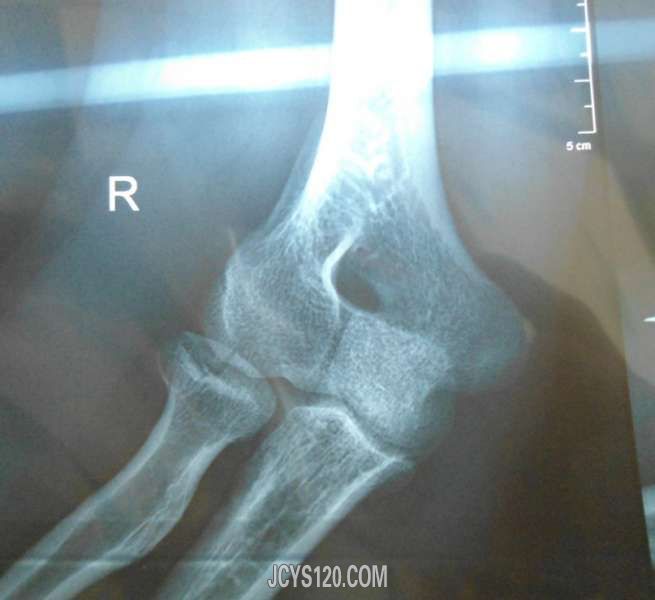

• 请版主帮助看下。 attach_img agree

• 浮生 2012-10-24

• 版主好,请帮看下X片,是我的一个病人。 王某,男,59岁,因咽部不适到本处看过病。最近常有胸闷感,这是近日X片。患者曾在煤矿上过几年班,近三年在某厂做花,工作环境有灰尘。请帮看下像不像矽肺。  阅读全文>